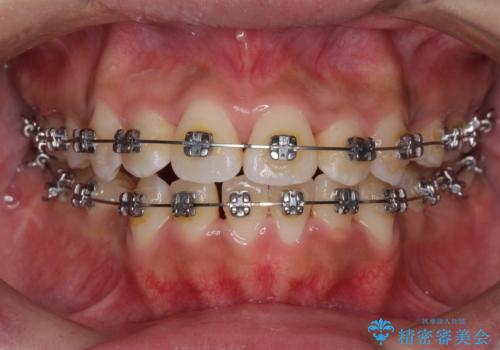

- メタルブラケット

- 2年1ヶ月

- 10-30回